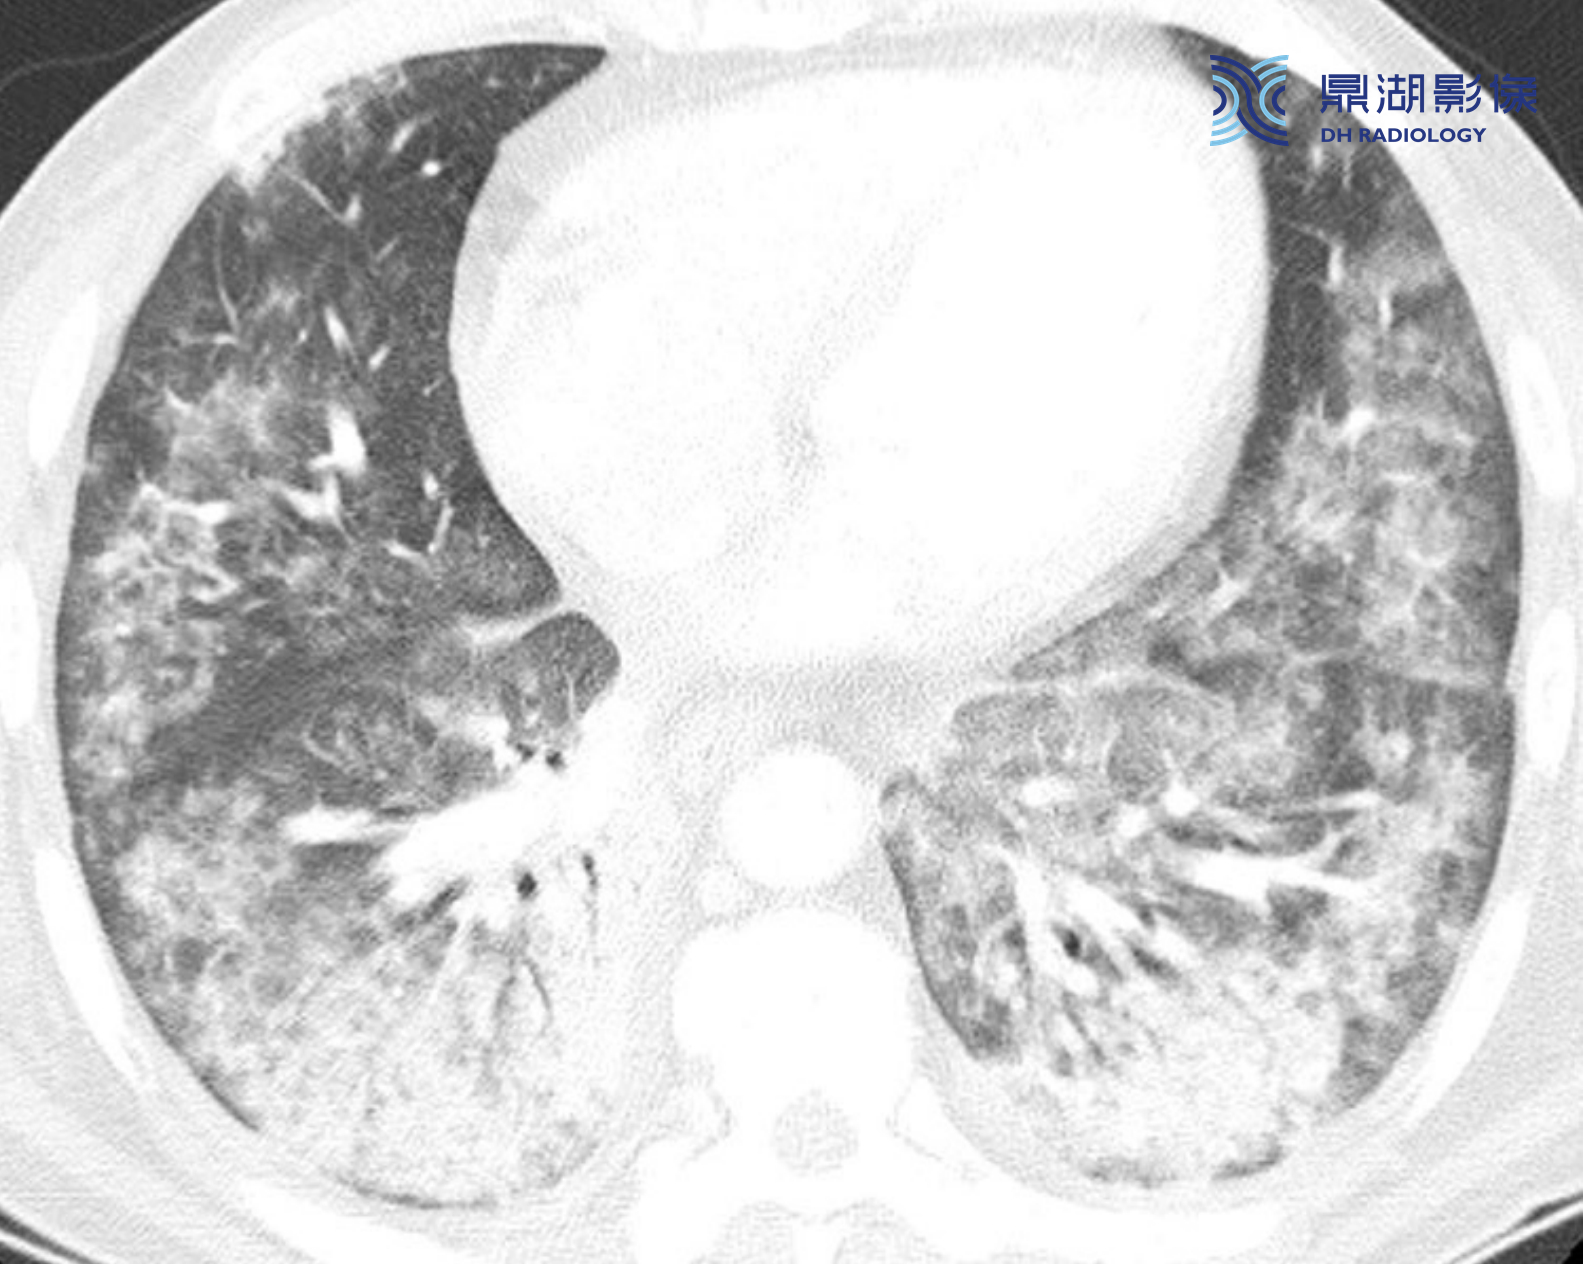

418746be9ace7259e448d41b7f80361b.png

急性呼吸窘迫综合征(ARDS)后纤维化。ARDS幸存者最终可发展为肺纤维化(ARDS后遗症之一)。这种纤维化典型分布于肺前部。

典型表现包括不规则网状影、牵拉性支气管扩张和(或)蜂窝征(箭)。